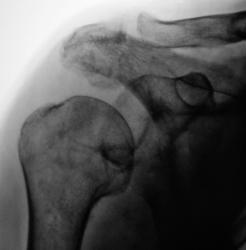

Травма 2 месяца тому. Двусторонний вывих плечевых суставов. Перелом акромиального отростка справа (застарелый). Откол фрагмента костной ткани от головки плечевой кости.